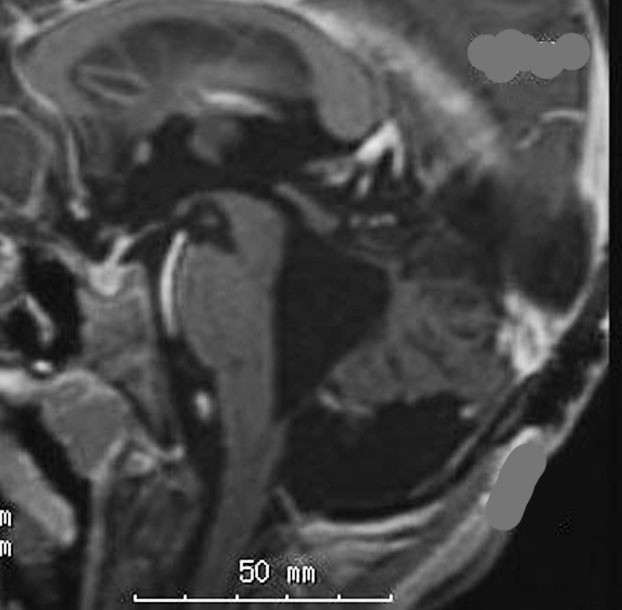

手術翌日のMRIです。小脳失調症状の出現はなく,抜糸してすぐに退院して普通の生活に戻れました。

この画像を見れば,後頭下開頭テント下法 infratentorial approach では,小脳切断しなければ腫瘍に届かないことが理解できると思います。